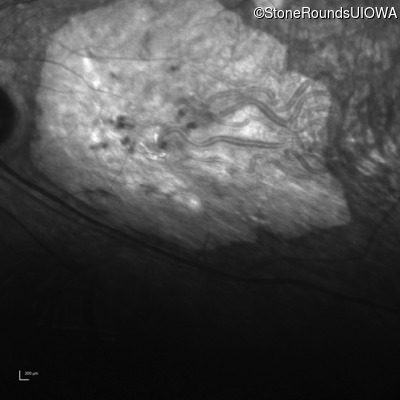

Infrared Fundus Photograph - Left - 20/160 sc

Exemplar